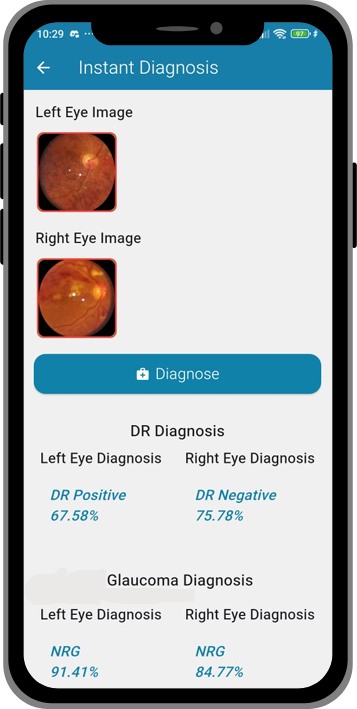

Lunera’s AI model scans the images for signs of DR & other retinal conditions.

3. Report

Instant results appear on the app, stored securely for doctors & patients.

4. Act

Doctors or caregivers can start early treatment or referrals immediately.

Q3: How accurate is Lunera?

A: Lunera’s AI has been validated on global datasets and achieved a 92.3% accuracy score, placing it among the top-performing DR detection methods.